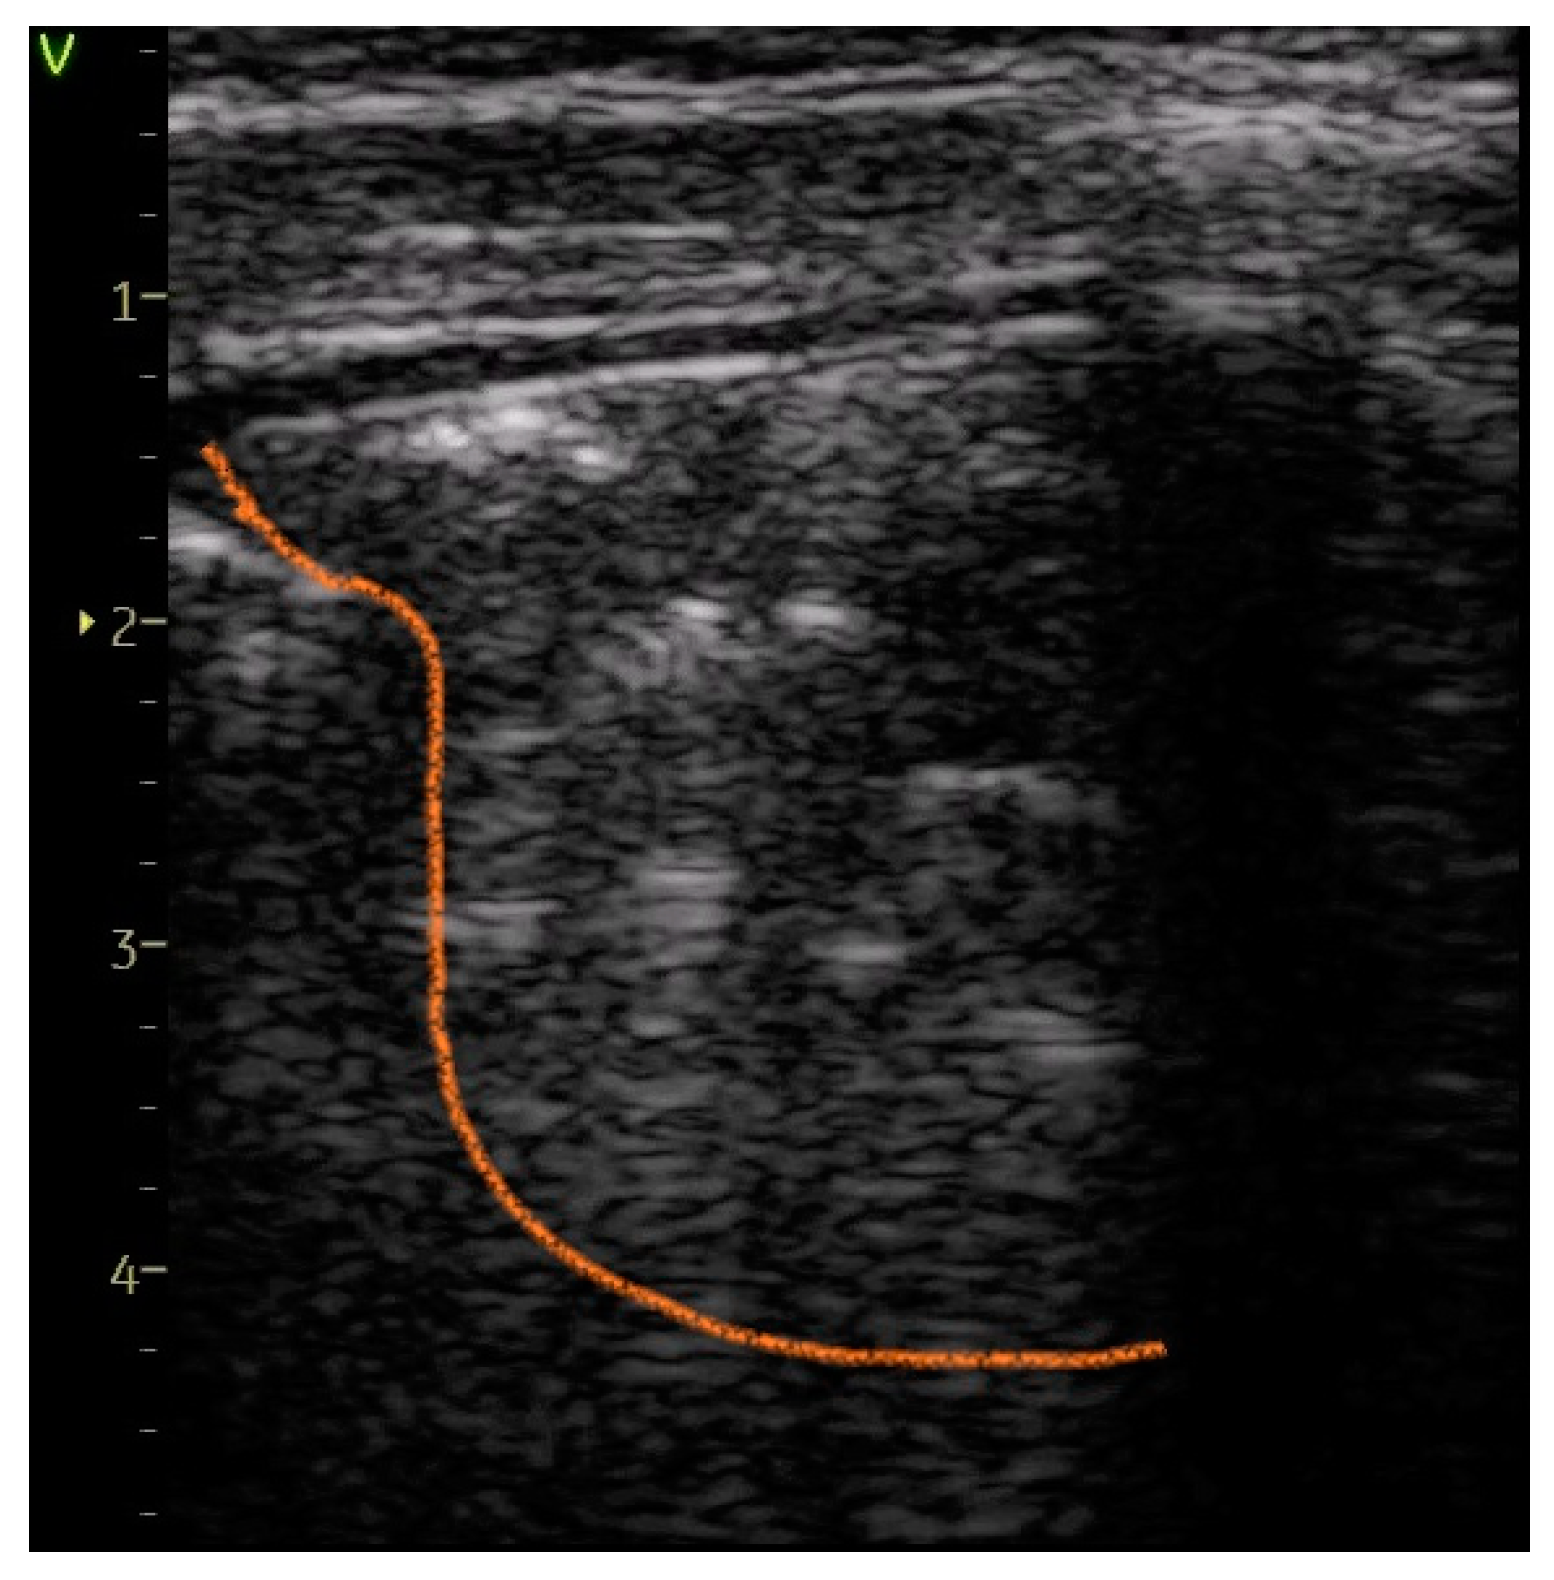

- A score of 3 was given for substantial peripheral consolidations wider than 1 cm, regardless of the presence of air bronchograms.

| Large consolidation of > 1 cm—Figure 7 | 0 | 5 (45.45%) | 45.45% | 35.31 | <0.0001 |